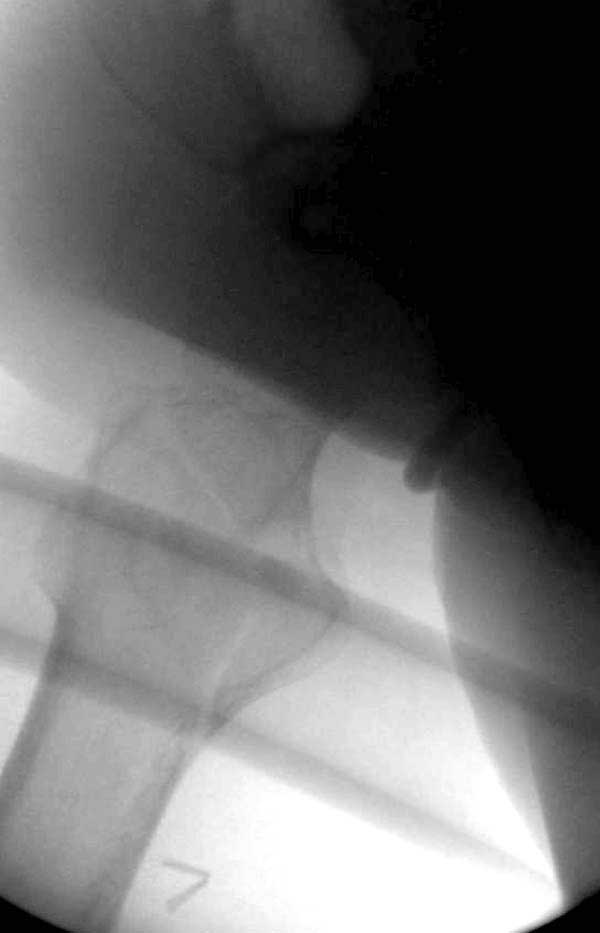

Третья операция-продолжения усилии "синьорами пэрами" по разрушению нормальной анатомии. Крест на головку! По видимому возраст позволяет биполярную конструкции, и при дефекте  calcar пошли на обычный цементный. Ягодичные мышцы потеряли связь с вертелом, т.е. отсутствует верхний удержатель, и результат “a Big Screw Up!” Снимки вызывают головокружение!

Если хирурги не устали от своих “творчеств”, тогда можно ре-оперировать с calcar replacement stem, и собрать остаток ягодичных мышц. Глубина и отстутствие артроза позволяет применить любой, биполярный или тотальный, хотя принять решение можно после ревизии ацетабулума.